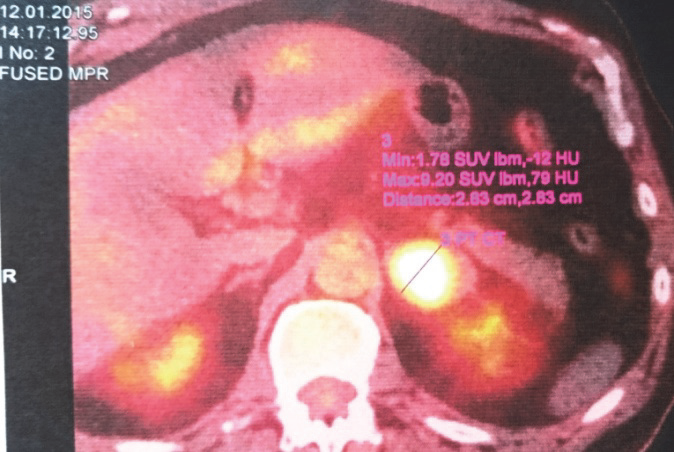

Hodnocení metastázy v levé nadledvině ze stejného období. Zmenšení nadledviny z 28 na 21mm je provázeno taktéž snížením metabolické aktivity původně vysoce aktivního ložiska na úroveň odpovídající akumulaci v okolních kosterních svalech: